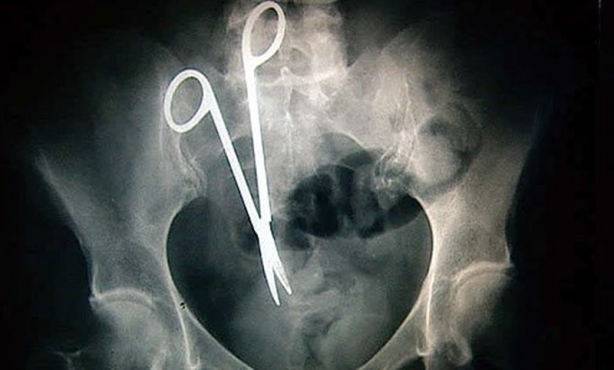

Makas yutan bir adam.

Hastanın midesinde unutulan bir makas...